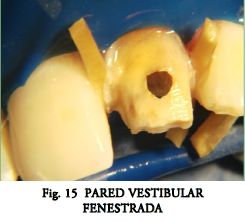

La recomendación usual del fabricante de cementar el poste y luego tallar la corona, puede dificultar el correcto posicionamiento en sentido mesio-distal o vestíbulo-lingual. Además impide apreciar el espesor de las paredes debilitadas por el tallado (usualmente la vestibular) (Figs. 14, 15, 16, 17). Por otro lado también complica el cambio de estrategia (habría que fresar el poste ya cementado).

Permite estimar de manera certera los espesores de paredes en el remanente coronario (Figs. 14, 15, 16, 17).